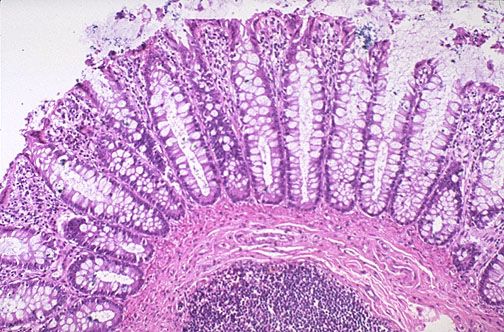

(10-15 ноября 2025 г., Воронеж, ВГМУ им. Н.Н. Бурденко). В рамках ФОРУМА состоялась Online-олимпиада по гистологии «Пищеварительная система».